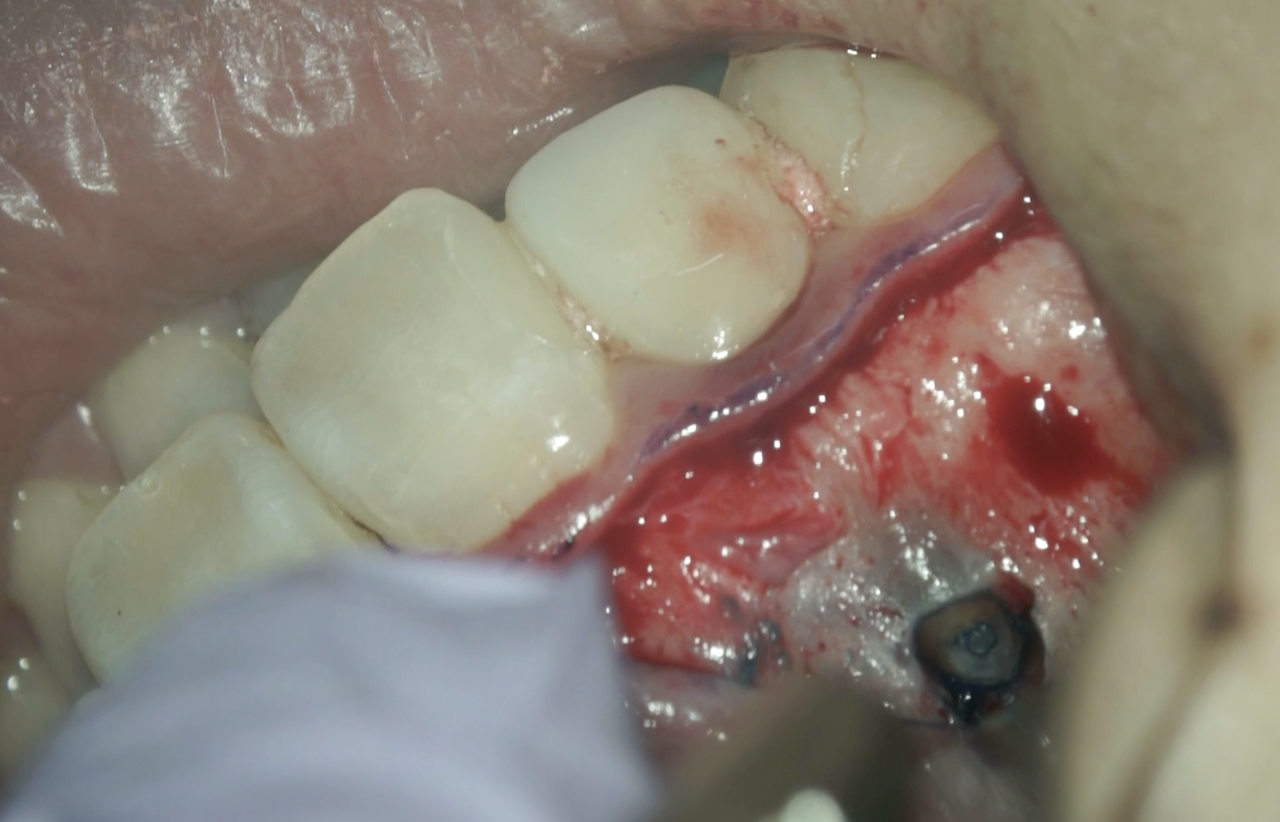

この切断面の根管の内部に存在するのは…レジンコアのレジンだ。

逆根管形成にはやや時間がかかるだろう。

逆根管形成して逆根管充填した。

術後にPA, CBCTを撮影した。

問題はないだろう。

いや、この謎の物体が取れてないじゃないか!?💢

ちゃんと取れよ!というあなた。

これが違和感の原因ならおそらくこの方は生涯違和感が取れないだろう。

その心は、

根尖から外に出したものはもう2度と全ては除去不可能なのだからである。

縫合して終了した。